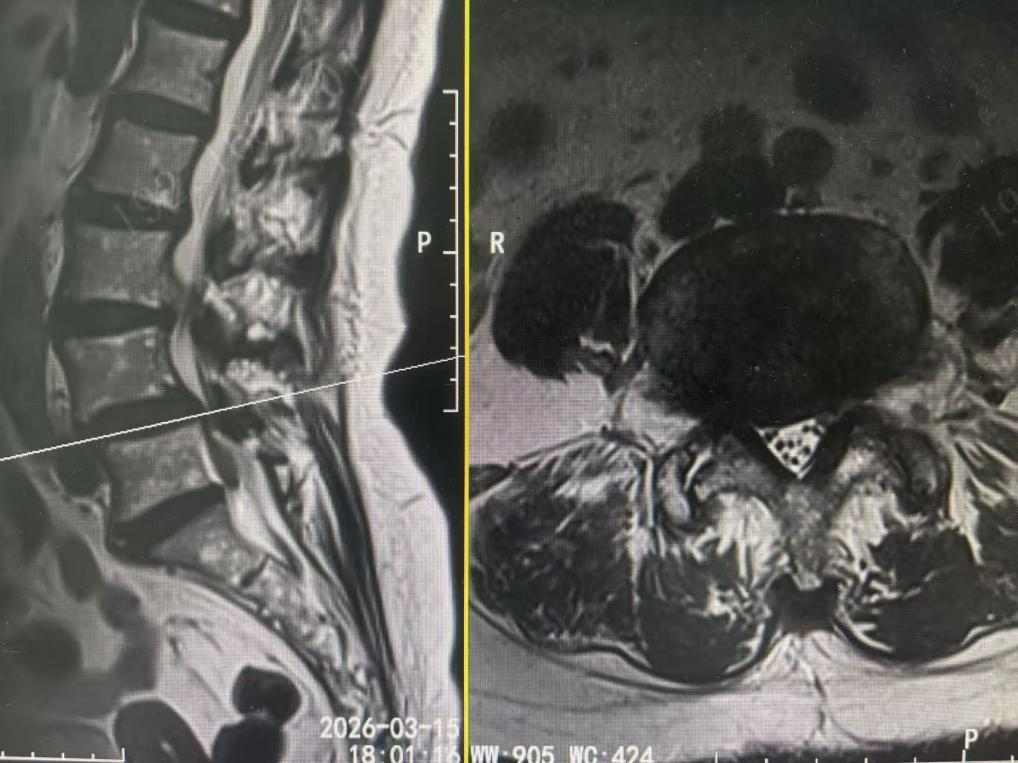

术前磁共振

腰椎间盘射频消融术并非传统意义上的开刀,而是一场在影像引导下的“精准狙击”。它的原理是什么?简单来说,它是在X线或CT的实时“导航”下,医生将一根直径仅约0.7毫米(类似缝衣针粗细)的射频穿刺针,精准穿刺至患者突出的椎间盘髓核位置。一旦针尖抵达病灶,射频仪通过针尖产生可控的高频电流,使突出部位的髓核组织内的胶原蛋白分子振动、摩擦生热(通常控制在60℃至90℃之间)。这一温度足以使致病的髓核蛋白凝固、变性、收缩,从而体积减小,即刻解除对神经根的压迫。同时,温热效应还能有效消除神经根周围的无菌性炎症,达到“一举两得”的效果。

· 诊断明确:影像学检查显示为轻中度的“包容型”椎间盘突出,髓核未脱出纤维环,且症状与影像学结果吻合。